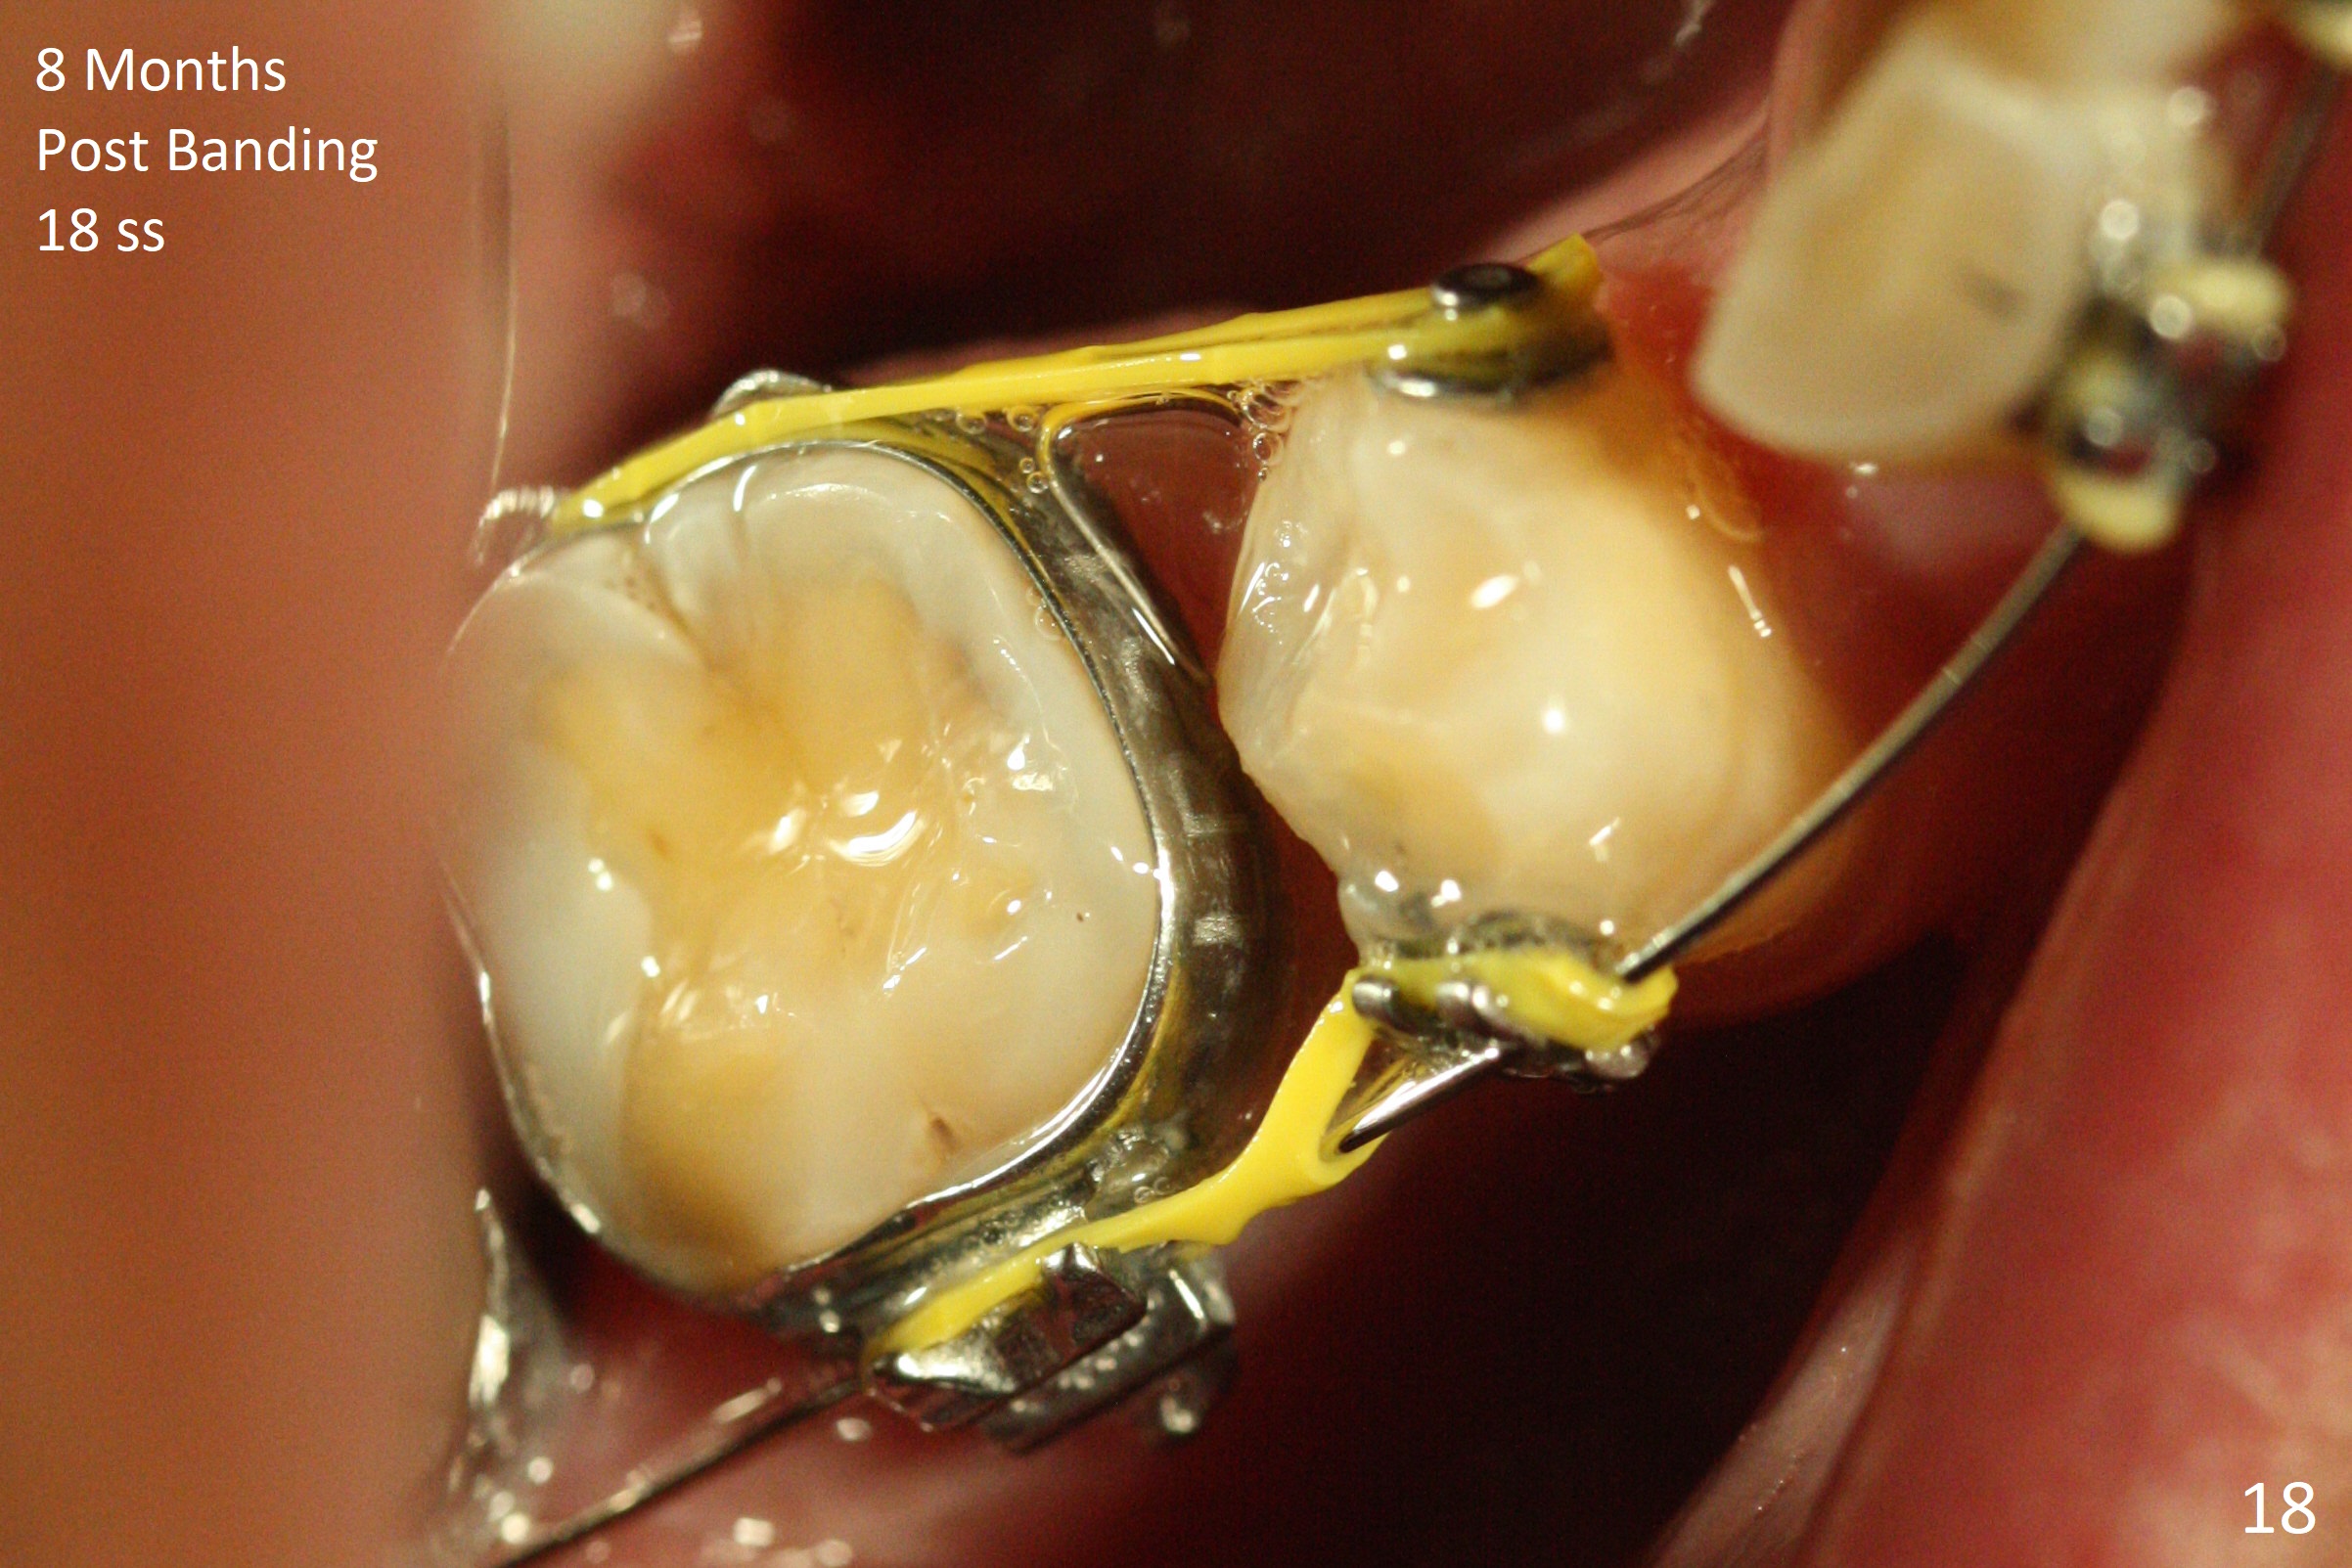

Severe crowding (Fig.1-7) appears to be alleviated especially 2 months after UR5 extraction. Diastemata seem to form mesial and distal to UR2 (Fig.8). Because of severe wear at UR3 (Fig.6), there is no bracket placement differential around it (Fig.8 (14 niti wire)). Lower bands and brackets are placed a week later (Fig.9-11). Because of tight space between LR4 and the opposing tooth (Fig.10), band adhesive is applied to L7 occlusal surface to open the bite (Fig.9). There is an abrupt kink of 12 niti wire between LL4 and 6 (Fig.11). The latter does not improve much in a month; the wires remain the same (Fig.12). For LL2, LR4 has been retracted for ~ 1 month (Fig.13). There is mild tension when 18 ss wire is inserted between LL4 and 6 five point five months post banding (Fig.14). UR4 has been distalized for a month using buccal power chains x3 resulting in rotation; to counter the rotation, a lingual button is placed with power chain x3 lingual and x2 buccal (Fig.15). With space gaining, it is time to finish definitive filling (Fig.16 *). Next visit check midlines, overjet, interdigitation, and molar classification. R4s distalize, but associate with rotation because of power chains buccal and lingual 8 months post banding (Fig.17,18). With the use of the same wires, power chains are applied lingual to continue distalization and rotation correction (Fig.20,21). Lingual buttons are placed at L2s buccalization (Fig.19) and mesialization (Fig.22,23). It appears that space should be created distal to LR3. That is that the lower anterior teeth should be shifted to the right, although it may be not appropriate for the midline.